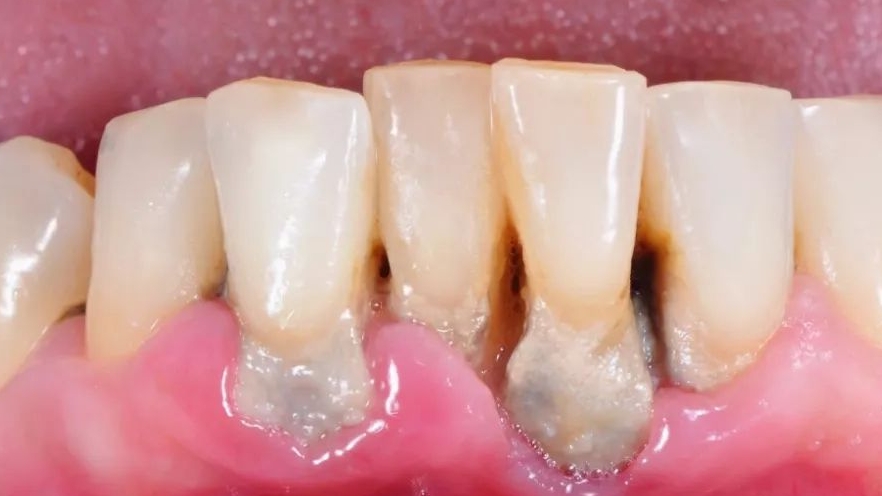

3.Characteristics: Darker in color (dark brown or blackish-green), harder in texture, firmly adhering to tooth roots like cement, and highly destructive to periodontal tissues.

Engine of Periodontitis: The rough surface of subgingival calculus serves as an ideal "sanctuary" for bacteria. These bacteria continuously release toxins, triggering gingival inflammation and leading to the formation and deepening of periodontal pockets.

Devourer of Alveolar Bone: Sustained inflammation gradually erodes the alveolar bone that surrounds and supports tooth roots, causing bone resorption and atrophy. Just as a tree loosens when the soil around its roots washes away, teeth become loose as alveolar bone is lost.

5.Gingival Recession: Teeth appear longer as the root surface becomes exposed.